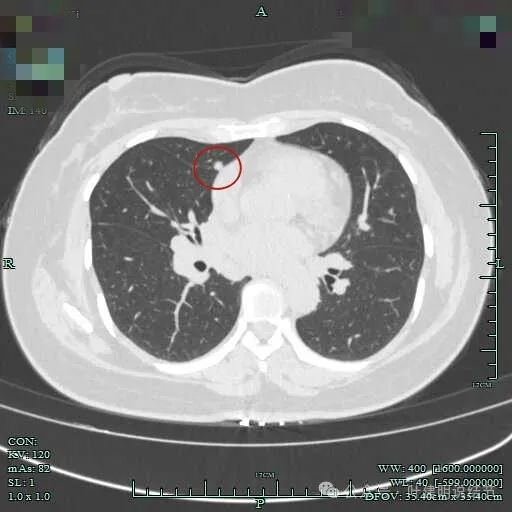

先看2023年1月时的影像:

右上叶贴着纵隔侧有实性结节,表面不平毛糙,有毛刺征,邻近细支气管扩张,纵隔胸膜略有牵拉,膨胀性不太明显。